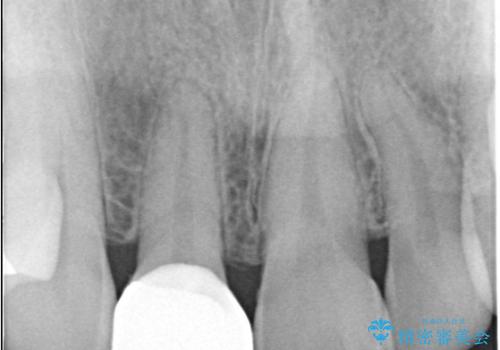

- 患者様は、前歯の被せ物の形や色が不自然で気になるというお悩みを抱えて来院されました。

診察の結果、既存の被せ物は古い素材で作られており、周囲の歯との調和が難しいことが分かりました。患者様とカウンセリングを重ね、アライナー矯正で歯列のガタツキを修正後、。より自然で審美的な仕上がりを目指してオールセラミッククラウンでの治療を提案しました。